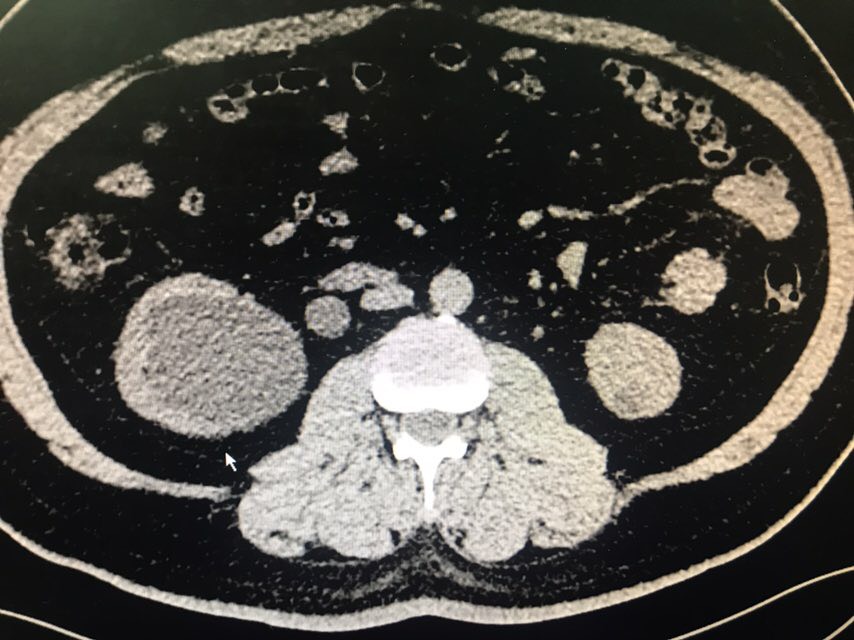

查体:无特殊。辅助检查:全腹CT(我院2018-8-6):右肾盂、肾盏及右输尿管上段明显扩张、积水;右侧输尿管置管。左肾盏区点状结石;双肾囊肿可能。膀胱充盈,壁稍增厚、毛糙,合并炎症可能,胆囊结石。脂肪肝;肝右叶小钙化灶。

从患者CT片子上看,患者右侧输尿管下段狭窄,输尿管支架管返折,因膀胱镜下未能成功取出,故行右侧输尿管探查术。手术顺利,术后给予曲克芦丁脑蛋白水解物注射液5ml治疗,患者术后恢复良好。